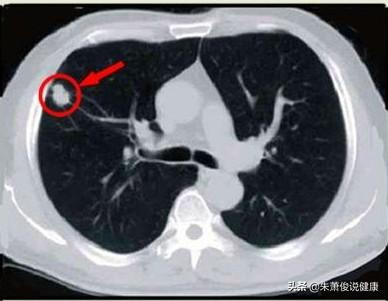

肺結節とは、肺にできる3cm以下の球状の病変のことで、胸部CTが健康診断に普及したことで、肺結節の発見率はどんどん高くなっており、違和感なく肺結節の検査を受けている人も多く、ネット上では「肺がんが怖い」と言われていますが、では結節の大きさはどれくらいなのでしょうか?

私たちはこの病気の診断の考え方を知っており、それから頭に戻って肺結節の話をする。肺結節とは、肺にできる直径3cm以下の円形または不規則な病変のことで、画像上では密度が増加した陰影として現れ、均質または不均一、単発または多発、境界が明瞭または不明瞭である。

肺結節の定義について、中国医学ガイドラインは次のように述べている:画像診断(胸部CT)により、直径3cm以下の限局性、円形状、密度増加した固形または亜固形の肺影が認められ、孤立性または多発性の可能性があり、肺無気肺、肺門リンパ節腫大、胸水を伴わない。

一般に、肺にできる直径3cm以下の密度増加影を肺結節と呼びますが、その危険度は大きさだけでなく、結節の形態、密度、増殖速度も合わせて判断する必要があります。

CT検査以前は、肺結節が発見される確率は0.2%以下であり、発見される結節の大きさは基本的に1cm以上であったが、CT検査の普及に伴い、肺結節が発見される確率は飛躍的に上昇したが、どの程度の大きさの肺結節であれば、あるいはどのような肺結節であれば、より危険なのかが、現在特に関心の高いテーマである。

第一に、肺結節の区分については、現在、8mm以上3cm以下の肺結節を典型的な肺結節と呼び、8mm未満の肺結節のみを小結節と呼んでいる!

第二に、肺結節の大きさと良性・悪性のリスクの程度には相関関係がある!一般的に、5mm未満の肺結節が悪性である確率は0~1%、5~10mmが悪性である確率は6~28%、20mm以上が悪性である確率はかなり高く、ほぼ60%以上と考えられており、これはすりガラス状の肺結節の悪性の程度と同様である!

まず、強調したいことがある:肺結節が危険であるかどうかは、その大きさだけでなく、肺結節の特徴にもよる。肺結節の数、密度、変化および徴候内訳は以下の通り。

2 肺結節の大きさ

肺結節の大きさは一般に直径で測定され、測定された直径の大きさによって大別される:

1.ミクロノジュール:直径<5mm。

2.小結節:直径5~10mm。

3.肺結節:直径30mm以下。

4.腫瘍:直径30mm以上。